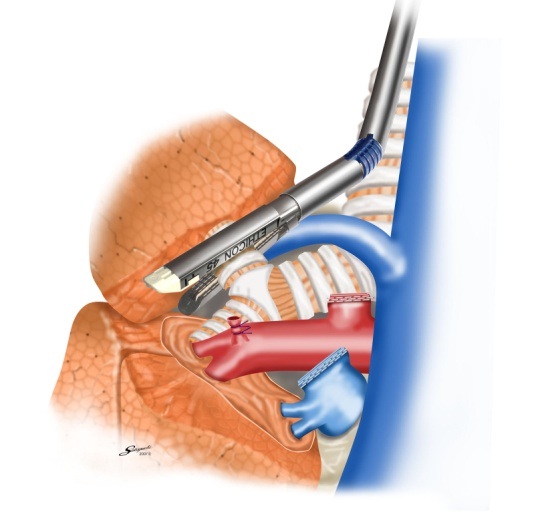

胸腔鏡手術の実際(右肺上葉切除時の自動縫合器使用例)

肺静脈切離

肺動脈切離

気管支切離

葉間切離

肺癌その進行度により病期IからIV期に分類されます。また、肺癌は非小細胞肺癌(腺癌、扁平上皮癌、大細胞癌、腺扁平上皮癌、腺様嚢胞癌、粘表皮癌など)と小細胞肺癌に分類することができます。どの病期または組織型にあてはまるかにより治療法は異なります。非小細胞肺癌の場合、I期、II期、IIIA期の一部であれば手術療法の適応となります。なかでもI期症例は胸腔鏡手術の良い適応とされています。当科では癌の進展状況、全身状態、心肺機能など十分考慮した上で、手術可能であるか、術式をどうするか(胸腔鏡下手術の適応など)さらには術後補助化学療法を行うかを呼吸器内科医と連携をとりながら肺癌を治療していきます。また、当科は胸腔鏡手術いわゆる内視鏡手術を積極的に行い、患者さんの体に優しい手術を得意としています。当院で施行した胸腔鏡下右肺葉切除術+縦隔リンパ節郭清の術後の創部の写真を以下に示します。まず、5cm大の小開胸創のみの胸腔鏡手術で、患者さん側に対して侵襲が小さく、創部痛も極めて最小限に抑えます(Single Incision Thoracoscopic surgery:SITS写真1)。さらに、胸腔内の状況に応じて3つないし4つのポート孔から手術を行う(いわゆる完全胸腔鏡手術:Pure Video Assisited Thoracoscopic surgery:Pure VATS写真2)または、小開胸創(5から 10cmサイズ)と1つないし2つのポート孔から行う手術(Video Assisted Thoracoscopic Surgey:VATS写真3)を行います。当科での胸腔鏡手術は1)手術の大部分がモニター下で、2)小開胸創のサイズは5から10cm(術者の手が胸腔内に挿入不能なサイズ)、3)肋骨切除がなされない手術と定義しています。胸腔鏡下手術とは胸腔鏡(カメラと光源を兼ね備えた器具)を用いて視野を確保し、胸腔鏡や自動縫合器、鉗子などを挿入し、手術を行う手術法です。呼吸器外科での胸腔鏡手術の厳密な定義はいまだ定めれてはいませんが、当科では患者さんに対して上記の術式で最大限低侵襲になるよう心掛けております。また、進行癌に対しても限りなく完全切除(腫瘍を完全に切除すること)を目指して手術を行います。